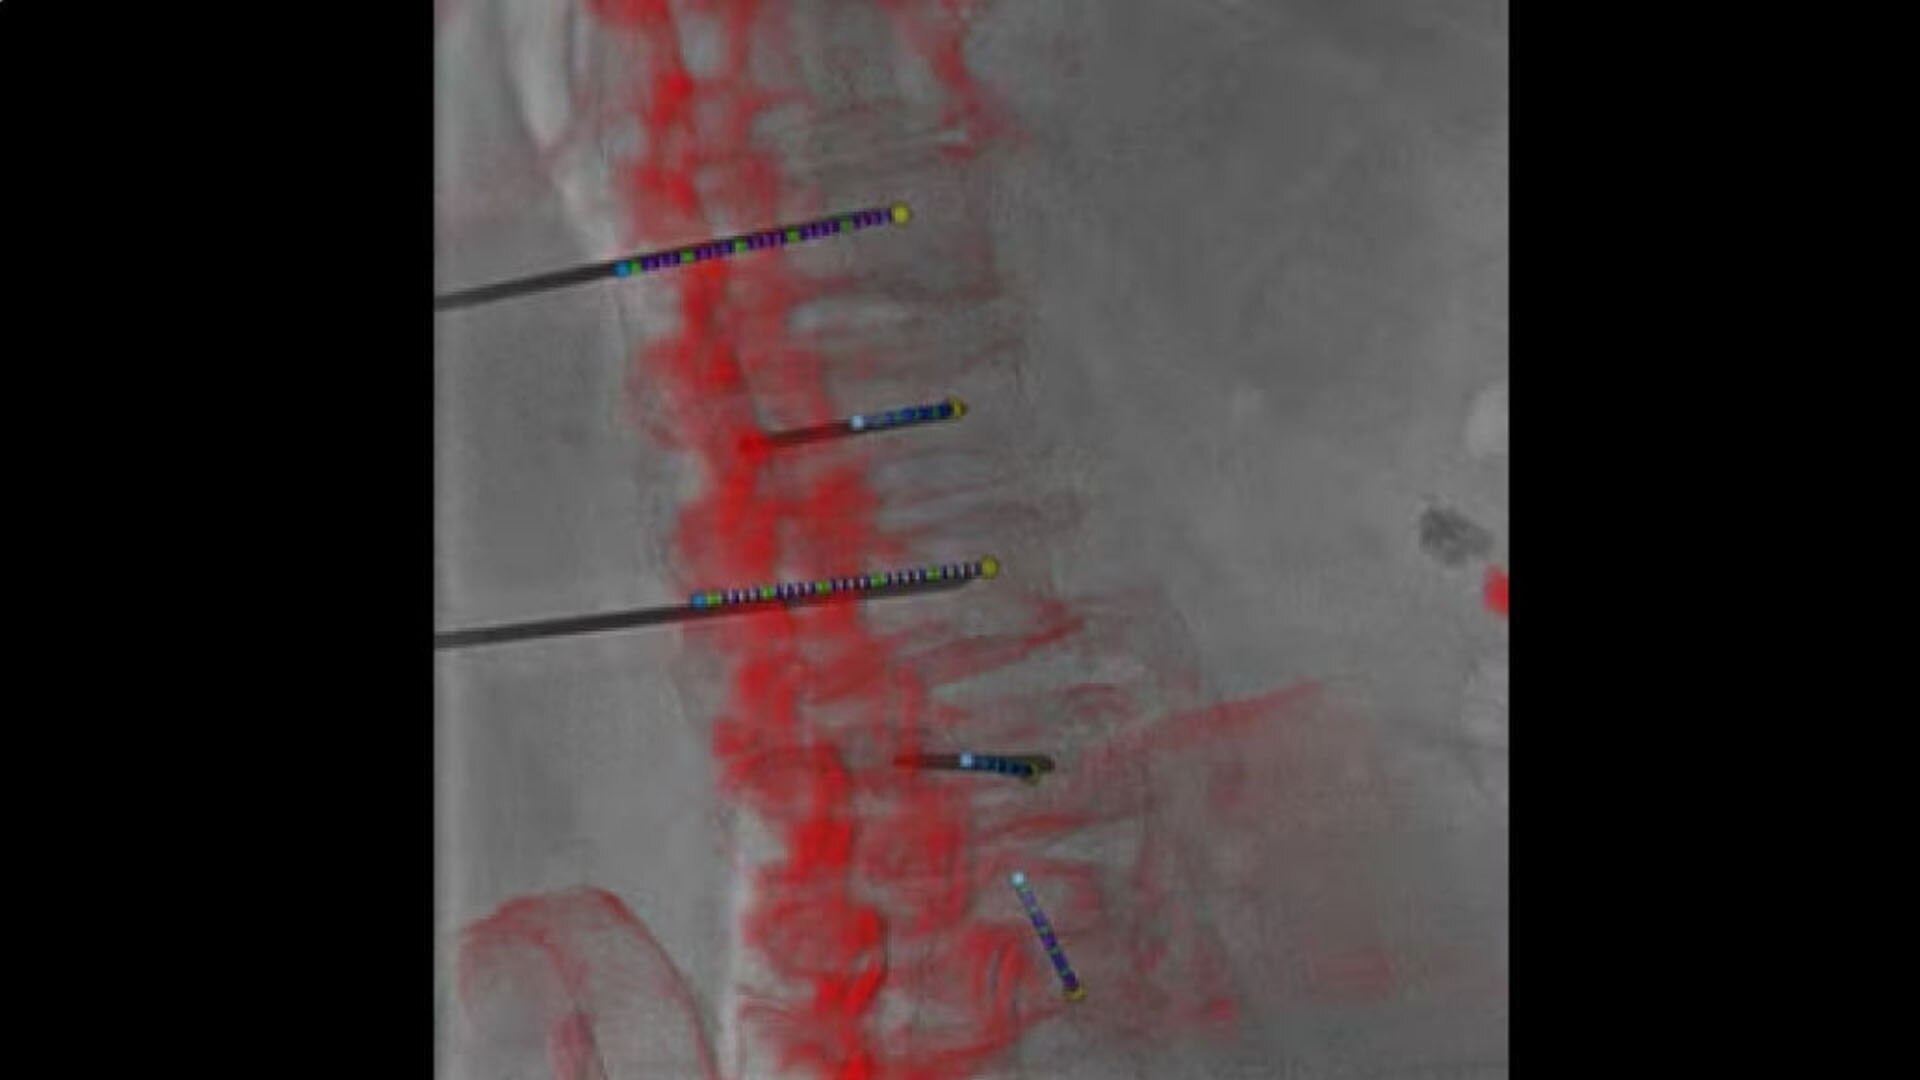

Plan

Define the pathway

Define optimal needle entry points and pathways directly on oblique CBCT cross sections.

hero_sticky_scrolling_1-ci-en